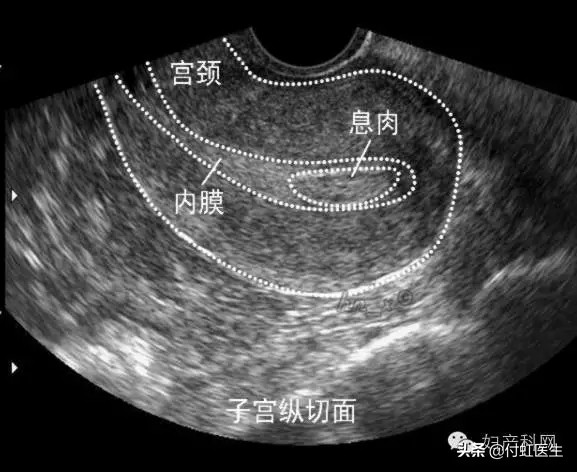

比如女生主要表现为子宫出血、绝经后不规则出血、不孕,也可表现为周期缩短、经期延长等。如果B超检查发现宫腔内见不均匀低回声或稍高回声周边高回声,与子宫壁边界清楚,形状呈椭圆形, 内部可见大小不一的等透声区;子宫内膜与息肉相连的纤维蒂清晰,子宫内膜弧线偏移; 可见子宫内少量积液,彩色多普勒超声检查显示部分息肉内部可见星点状或条状血流信号。

这个时候,我们就会下“子宫内膜息肉”的诊断。当然子宫里面的到底是不是息肉?还需要医生做宫腔镜检查,手术切除送病理,病理诊断才是金标准。